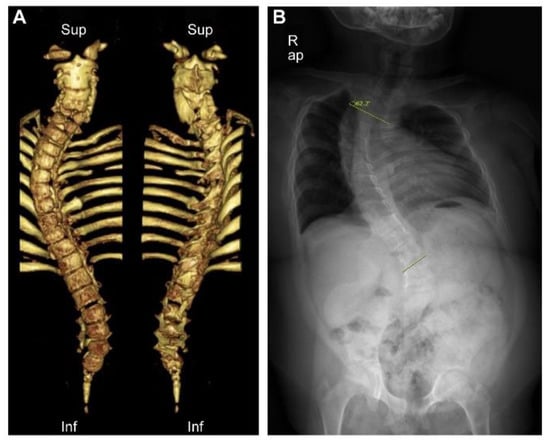

From infancy to pre-school age, she suffered from repetitive respiratory infections, atelectasis, and chest retraction. She was hospitalized several times and had two respective events of intubation, followed by barely successful extubations. During her childhood, her morphologic features were prominent, with facial dysmorphism of a short nose, depressed nasal bridge, limited neck movement, low-set hair line, short stature, bell-shaped thorax, and protruded abdomen. Computed tomography (CT) of the whole spine and plain radiography showed multiple skeletal anomalies (Figure 1).

Figure 1.

Three-dimensional computed tomography and plain radiography of the whole spine. (A) Multiple anomalies of the spine and the sacrum, including fusion of C2/3, C4/5 vertebra, butterfly vertebra of C5 to C7, dysraphism of C1, C5, C6, and T8, and hypogenesis of the sacrum, were notable. (B) Severe scoliosis of Cobb angle of 62°, decreased number of ribs, and downward tilt of ischiopubic rami were identified.